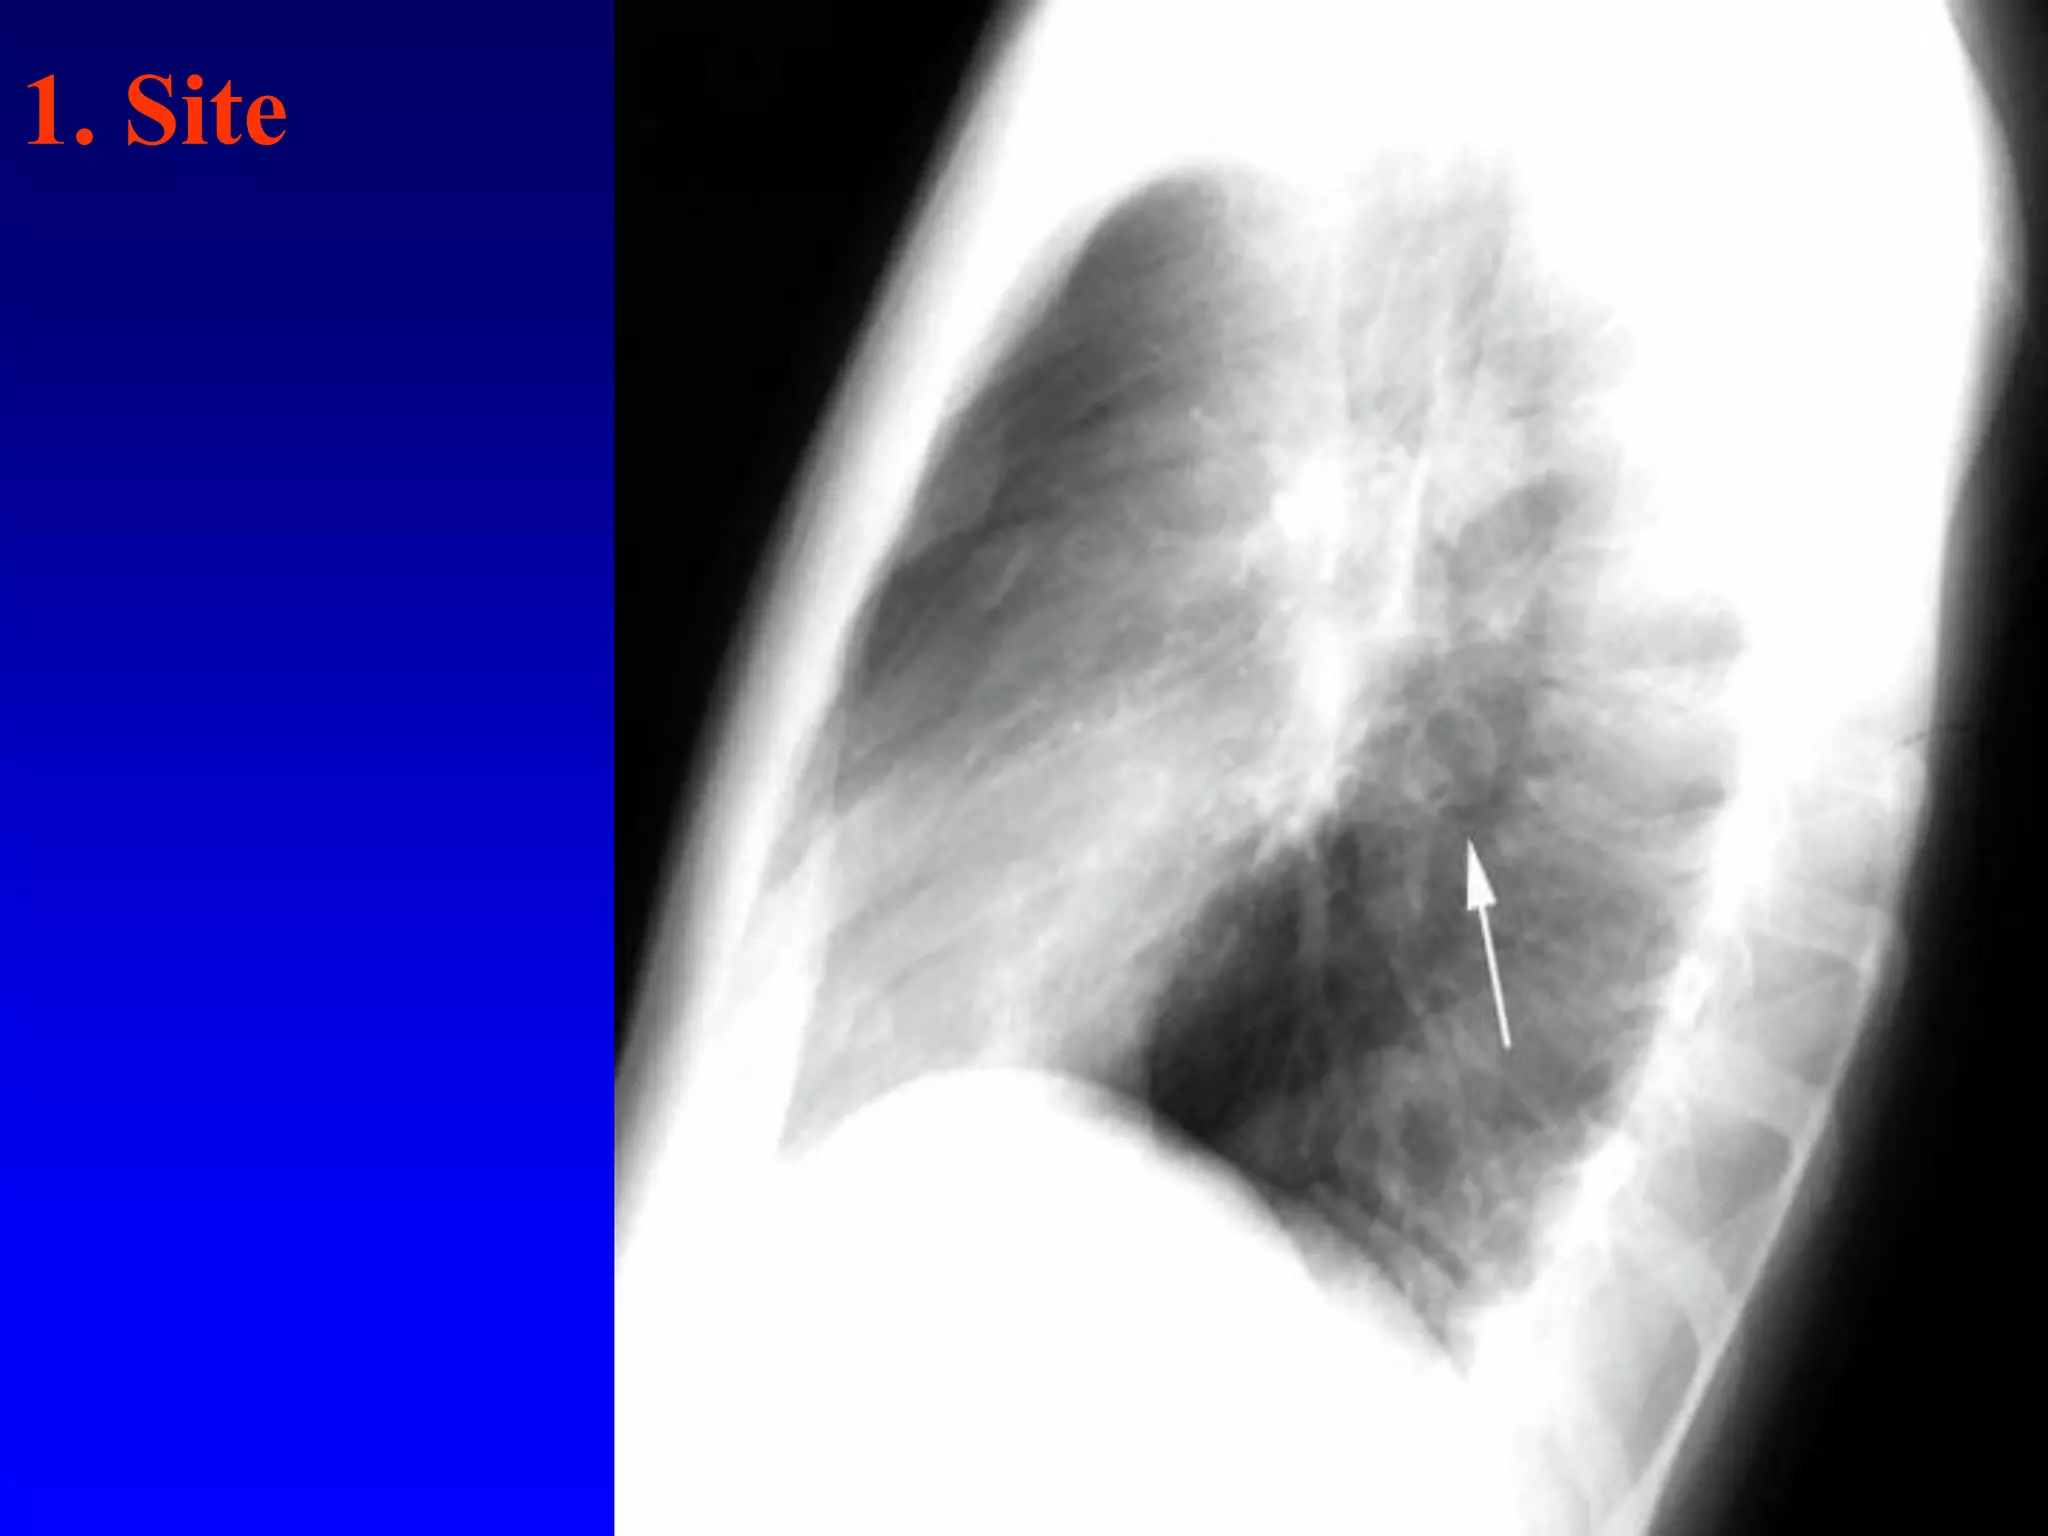

1. Site

A cavity in apicoposterior segment of left upper lobe